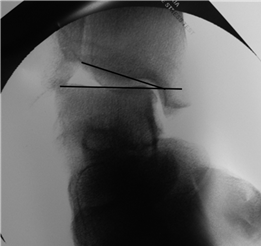

Clinical & Radiographic Imaging Archive

Clinical Image